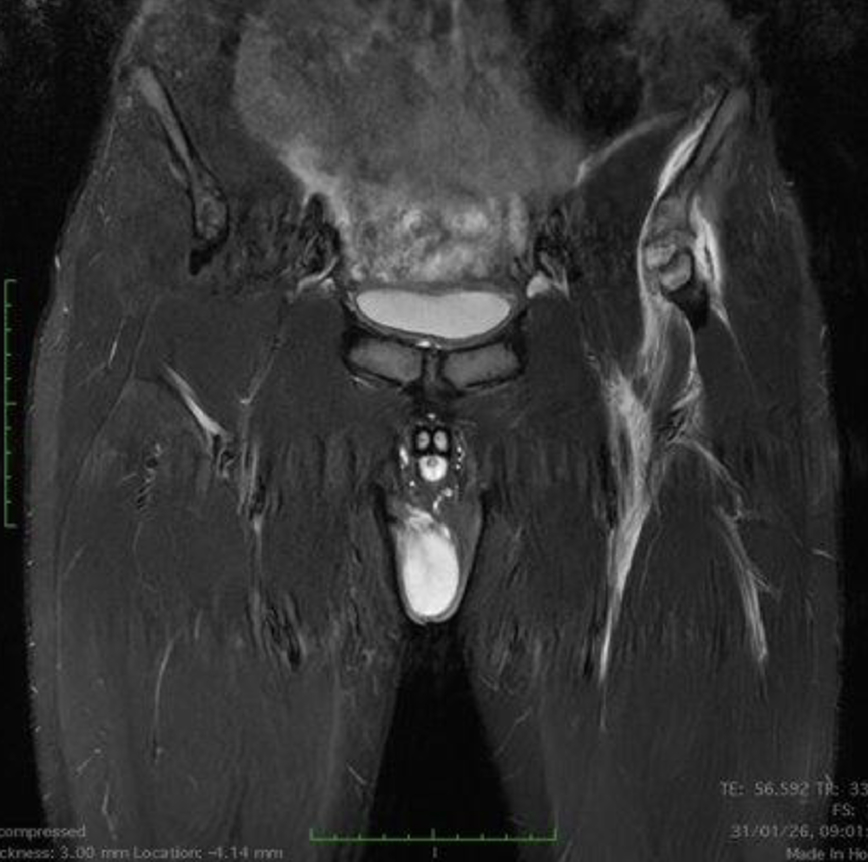

La velocità di progressione della fibrosi cardiaca: un nuovo orizzonte

La velocità di progressione della fibrosi cardiaca emerge come un nuovo e cruciale indicatore prognostico nella cardiomiopatia ipertrofica. Un recente studio evidenzia come l’LGE rate sia più predittivo degli eventi avversi rispetto alla semplice estensione della fibrosi, aprendo nuove prospettive per il monitoraggio e la gestione terapeutica dei pazienti.